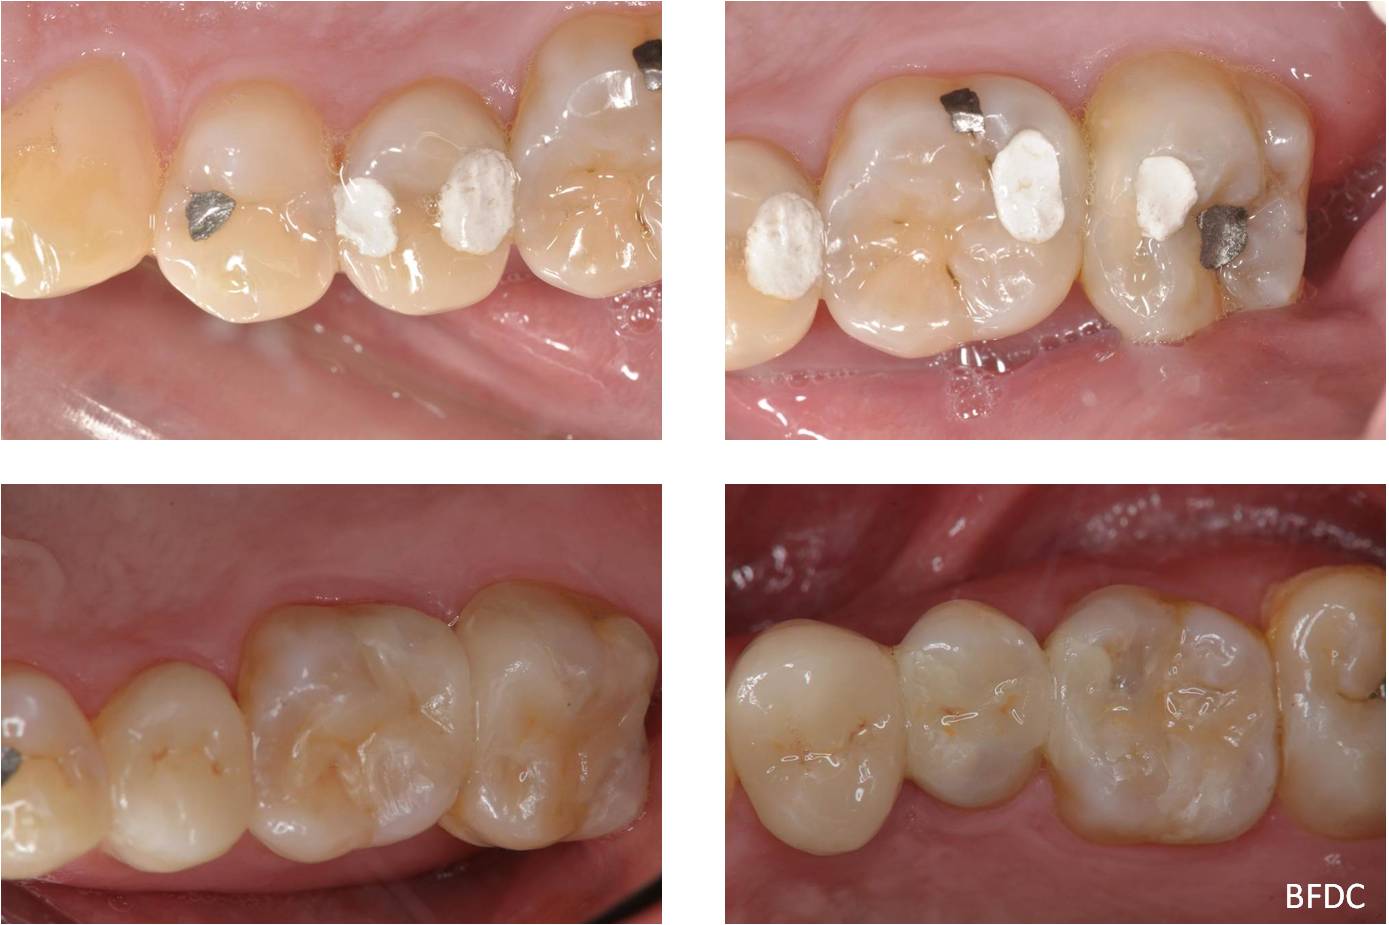

陶瓷崁體及冠蓋體-蛀牙-#1516172526 大範圍的補皮,該如何選擇,嵌體的方式就適用於大範圍的填補,因為它是一體成形, 嵌體材質多種,以往才會使用黃金合金,但因價格昂貴且顏色太過突出,因此現在多使用玻璃陶瓷二氧化鋯等材質的全瓷冠。嵌體有其優勢,因一體成形的材料,硬度和穩定性都較高,不用一點一點填補,減少下方凹陷重複蛀牙的危機,也不會變形或染色,美觀度高很多。 #1516172526蛀牙 #1516172526蛀牙 崁體及冠蓋體修形 安裝模型至咬合器 嵌體及冠塊體製作 陶瓷崁體及冠蓋體 黏著後 黏著後X光 術前、術後比較 嵌體有其優勢,因一體成形的材料,硬度和穩定性都較高,不用一點一點填補,減少下方凹陷重複蛀牙的危機,也不會變形或染色,美觀度高很多。

能避免片狀樹脂造成的,下方重複蛀牙,或彈性大造成咬合不舒服的問題,若有多顆牙齒填補,或坑陷較大者,如牙齒已蛀超過1/2或2/3者,才建議使用此種方式。